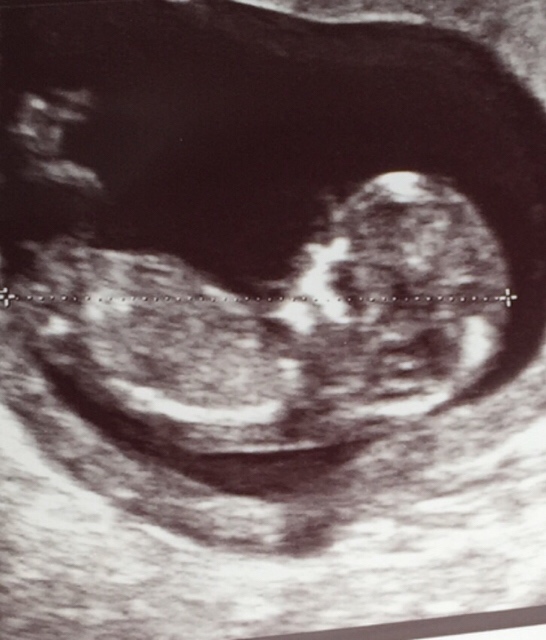

Ainiin mä unohdin silloin laittaa ultrakuvaa kun larissa sillon pyyteli. Nyt tosiaan aikaa jo ultrasta ja yritän torstaina jos neuvolassa kurkattais masuun. Äsken taas kuuntelin sydänääniä <3

Anskusella ihana pieni ihmisenalku <3

Asnkusella ja pepellä oli suloiset ultrakuvat.

Ihania kuvia pepellä ja anskulla :Heartred

Pepe, siellä myös ihana pikkuinen <3

Anskunen ja Pepe, aivan ihania ultrakuvia teillä! :Heartred

Ihania ultrakuvia teillä <3

Anskunen: ihana kuva! Ja onnea vielä kerran!

PepeXXL: onnea sinullekin ja tosi ihana köllöttelee siellä!

Pepe, sullakin ihana kuva! Nauti koko sydämmestä loppu raskaus<3